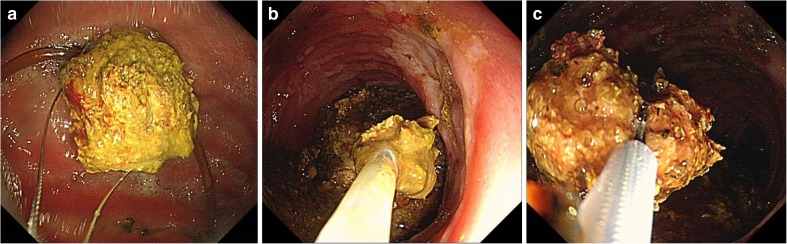

He was first treated with nasogastric tube intubation, intravenous fluid, and proton pump inhibitors after a presumptive diagnosis of duodenal obstruction caused by a persimmon phytobezoar. Initially, we tried to endoscopically remove the phytobezoar, but this was unsuccessful because the surface layer of the persimmon phytobezoar was too hard to break through with endoscopy forceps (FG-47L-1; Olympus, Tokyo, Japan). Then, we decided to attempt administering two cans (500 mL) of Coca-Cola (Coca-Cola Co., Hangzhou, China) every 6 h according to the method described elsewhere [6]. Two days later, EGD demonstrated that the persimmon phytobezoar was much softened and it was smaller than previously noted. We performed direct endoscopic injection of Coca-Cola into the persimmon phytobezoar. However, 4 days passed, the persimmon phytobezoar was still in the duodenum. An endoscopic injection of Coca-Cola was tried again. Five days later, we fragmented the persimmon phytobezoar by endoscopic forceps and polypectomy snares (MTW Endoskopie, Wesel, Germany) and then removed the fragments by a retrieval net device (MTW Endoskopie, Wesel, Germany) until the persimmon phytobezoar was broke into pieces (Fig. 2a–c). After the treatment, the patient could have some liquid diet and he gradually was able to eat properly. The third day after the treatment, he resumed a normal oral diet and was discharged home.

Fig. 2.

Endoscopic images of the process of fragmenting the persimmon phytobezoar by endoscopic forceps